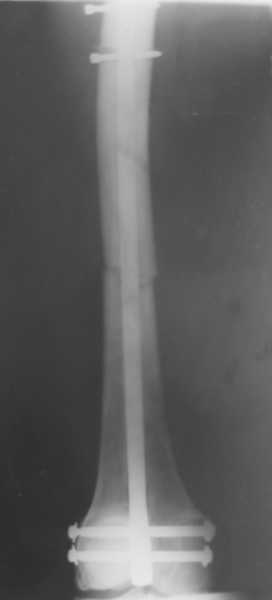

Здравствуйте , уважаемые коллеги. Обратился пациент, мужчина 42лет. для дальнейшего

лечения. Травма 11.09., ДТП.

15.09 проведено оперативное лечение (Блокирующий стержень левого

бедра - статическая система. Открытое вправление вывиха в суставе

Лисфранка и фиксация мет. фиксаторами.)

1. По бедру... Стержень конечно тонковат, торчит в колено..не совсем ясно, что там с прокстимальным блоком(... Если не будет нагрузки, получите замедленное стащение, потом когда датите нагрузку получите перелом винтов (в лучшем случае), штифта - в худшем(

>>>Стержень конечно тонковат, торчит в колено...

Видимо не просто так он торчит, а его специально не добили, чтобы мыщелки "зацепить" на обе стяжки.